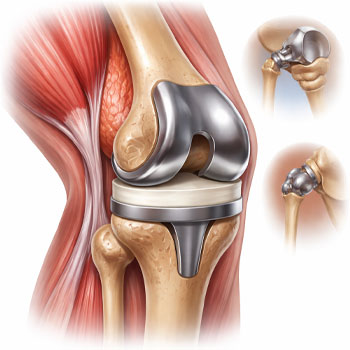

What orthopedic services are available?

We provide advanced orthopedic care including joint pain treatment, fracture management, arthritis care, and minimally invasive procedures with expert specialists at Jayabhrathi Multi Specialty Hospital